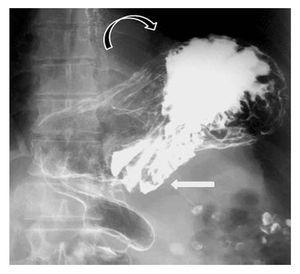

Hombre de 75 años con historia de dolor abdominal inespecífico crónico que ingresó a urgencias con un cuadro de pocas horas de evolución caracterizado por dolor torácico y epigástrico intenso, irradiado hacia la espalda y asociado a náusea sin vómito. Al examen físico se encontró dolor abdominal en epigastrio sin datos de alarma. Los estudios de sangre fueron normales. En la radiografía de tórax se encontró una imagen de nivel hidroaéreo en el hemitórax izquierdo. El protocolo de estudio se completó mediante una endoscopia y serie esófago-gastroduodenal en la cual se confirmó el diagnóstico de vólvulo gástrico órgano-axial (Figuras 2 y 3). El paciente fue llevado a la sala de operaciones para la realización de devolvulación y reducción gástrica hacia el abdomen, plastía diafragmática y funduplicatura tipo Toupet por laparoscopia.

¿ Figura 2. Serie gastroduodenal en que la flecha horizontal indica la localización de la unión gastro-esofágica. La flecha curva muestra el desplazamiento del estómago en su eje longitudinal.